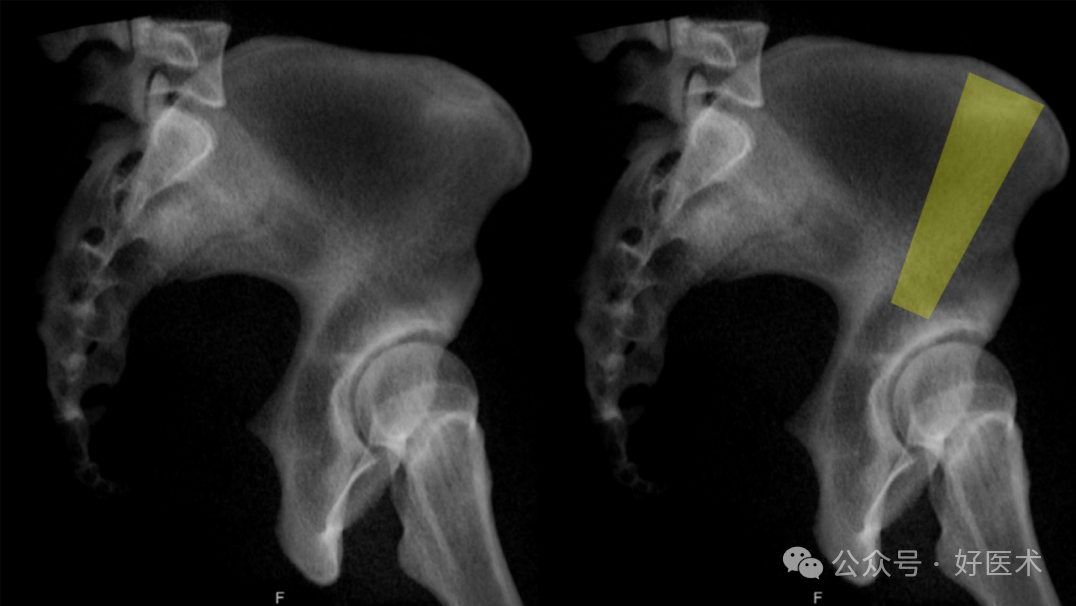

从髂嵴开始,位于髂前上棘(ASIS)外侧约4—5厘米处,延伸至髋臼的上方/上后穹窿的厚骨结构,且两层髂骨皮质之间有足够的空间,是潜在螺钉置入的另一个通道(图20)。

图20 臀中肌柱通道,从髂嵴开始,位于髂前上棘(ASIS)外侧约4—5厘米处,延伸至髋臼的上方/上后穹窿。

在初步分析中,该通道从髂嵴开始,位于髂前上棘(ASIS)后方5—6厘米处,前后跨度为6—8厘米。这条通道更多地用于 Schanz 螺钉插入,以便操作前柱骨折块,而不是用于固定骨折(Bishop)。它常用于放置前上骨盆外固定器。据报道,该通道的峡部在男性中为5.3毫米,在女性中为4.3毫米。它位于男性髂嵴下方27.6毫米,女性髂嵴下方36.3毫米,朝向坐骨结节方向。未观察到与骶骨发育异常的差异。